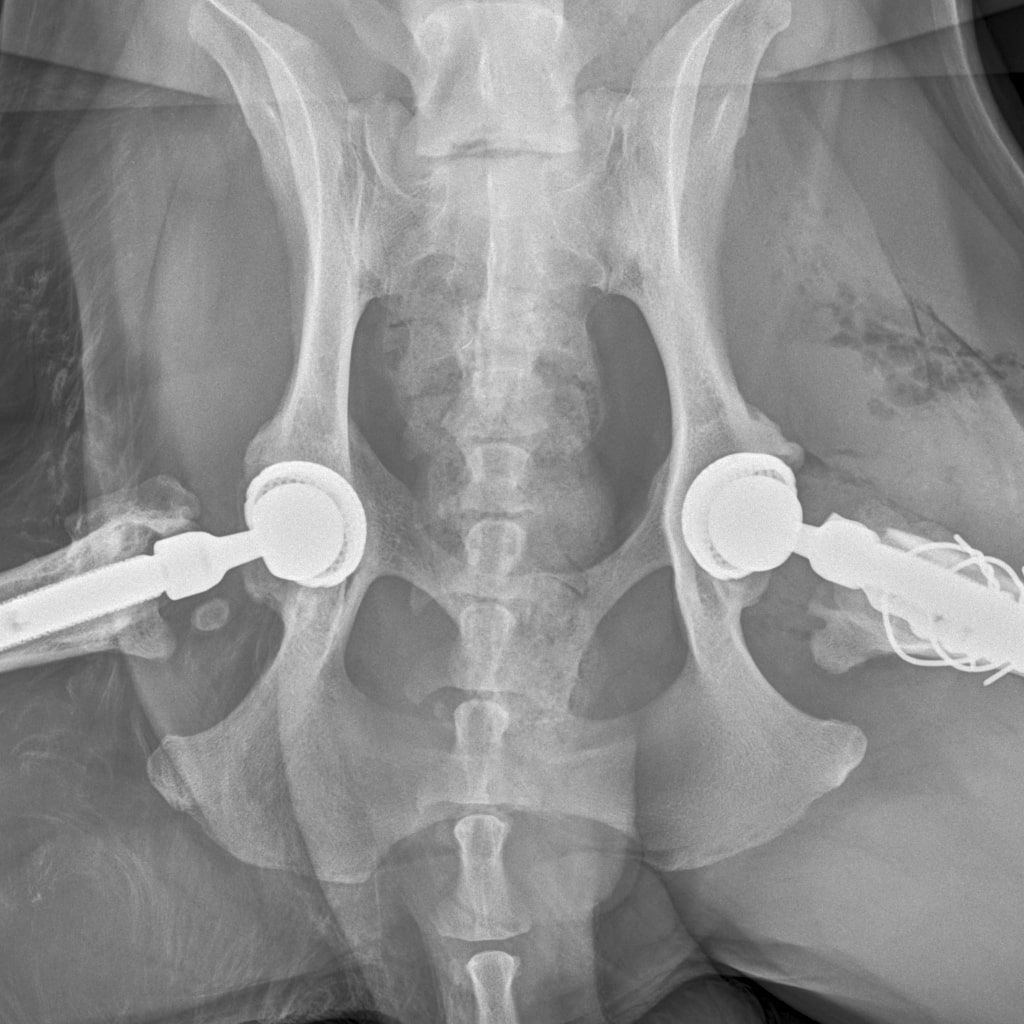

E358D56E-67BF-4D4C-B3F0-BF8F4089D7A2.jpeg

767DD36C-E2E2-41FB-9CCF-6940421D2BB2.jpeg

701487DA-D6D9-4CE0-B18B-EEB120E78EF2.jpeg

Мы ничего не оплачивали. Все включено.

За время противовоспалительной терапии снизилось воспаление и в левом тазобедренном суставе, но увы, форма головки бедренной кости и состояние шейки бедра , лучше не стали:(((

Операция однозначно нужна.

Снимки столь качественные, что их можно в учебник